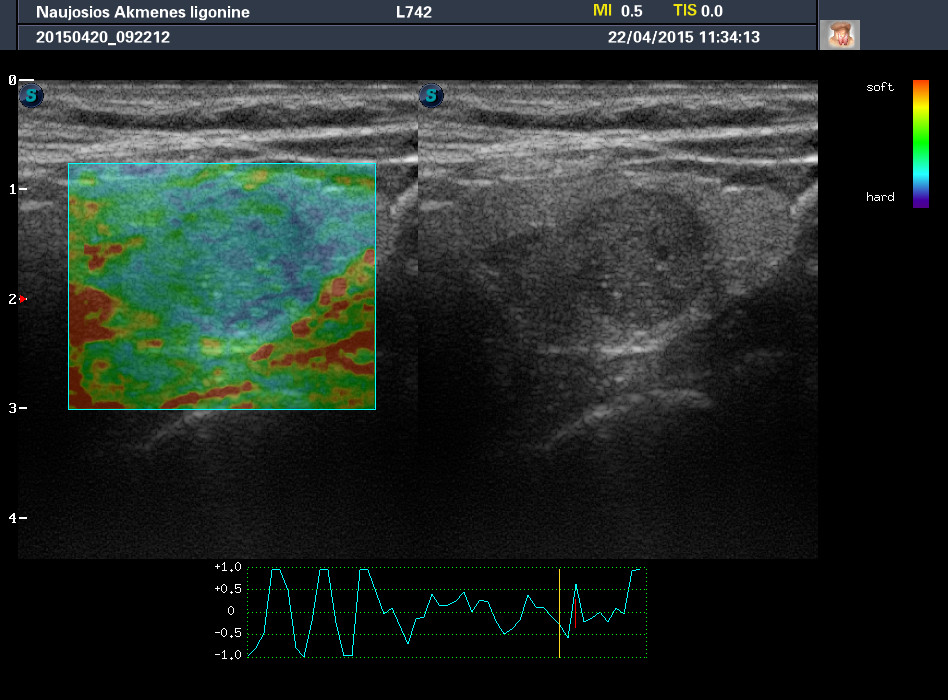

Случай 2

Женщина 61 год, жалоб нет. Рост узла за год +1 мм. Регионарные ЛУ не увеличены.

apr222015113351_29.jpg

apr222015113413_30.jpg

1-й узел злокачественный, а 2-й ,скорее всего, доброкачественный. Но,понятное дело, нужна пункция и было бы здорово узнать результат.

Согласна с Anastasia.:-) И,простите, что за исследование на сканах, не на видео? Я такого не делаю и,к сожалению, не знаю,как интерпретировать его(

Mattiola писал(а): И,простите, что за исследование на сканах, не на видео? Я такого не делаю и,к сожалению, не знаю,как интерпретировать его(

Эластография. http://www.medison.ru/si/art380.htm